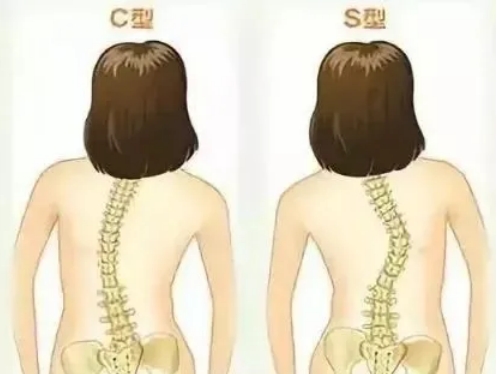

到底什么叫脊柱侧弯?简单理解,就是从背后看,孩子的脊柱不再是一条直线了。

首先是影响孩子的身形。 比如,脊柱侧弯可能导致孩子背部不平,胸廓畸形,长短腿等肉眼可见的变化。这些外形的变化会直接导致孩子自卑。尤其半大不小的孩子,爱玩爱闹,但也容易失去分寸。脊椎侧弯的孩子,就很可能会成为被同学嘲笑、甚至被同学排挤的对象。其次,影响身体健康。

而对女孩而言,脊柱侧弯可能导致两侧乳房发育不均匀。一些女孩还可能出现骨盆倾斜的情况。骨盆倾斜如果得不到干预,长期发展下去,严重的成年后可能存在孕育上的困难。